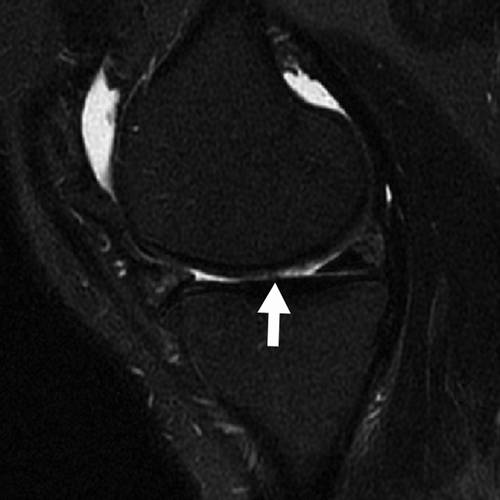

Incoming Term: 膝軟骨損傷, 膝軟骨損傷 手術 ブログ, 膝 軟骨 損傷 症状, 膝 軟骨損傷 サポーター, 膝 軟骨損傷 手術費用, 膝 軟骨損傷 原因, 膝 軟骨損傷 リハビリ, 膝 軟骨損傷 全治, 膝 軟骨損傷 mri, 膝 軟骨損傷 スポーツ復帰,